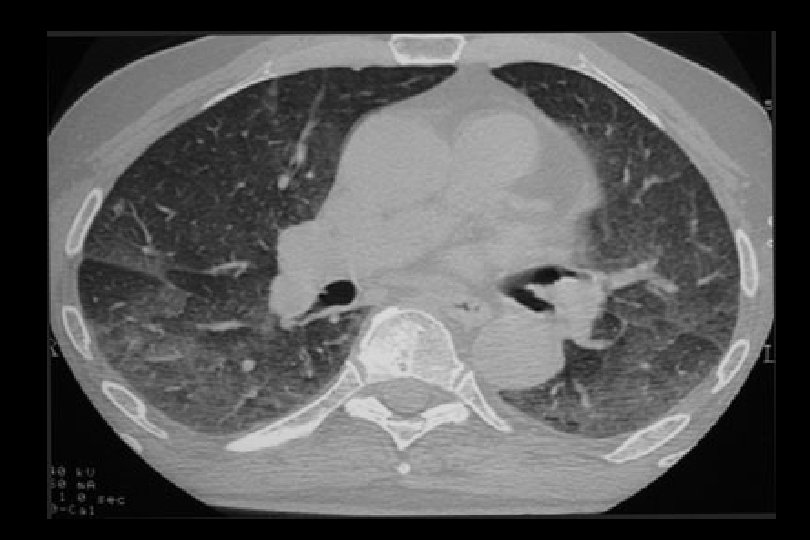

Tempo di comparsa anche superiore a 12 mesi 43 casi descritti in letteratura dal 2000 al 2004 (Pham et al, Transplantation 77, 2004) Dose dipendente? Sintomi Dispnea da sforzo Tosse secca Febbre (50%) Dimagramento Emottisi Strumentali Rx Torace: addensamenti bilaterali Vetro smerigliato TC: Infiltrati alveolo interstiziali Broncoscopia: Alveolite linfocitaria Emorragia polmonare Biopsia: Polmonite organizzata Bronchiolite obliterante